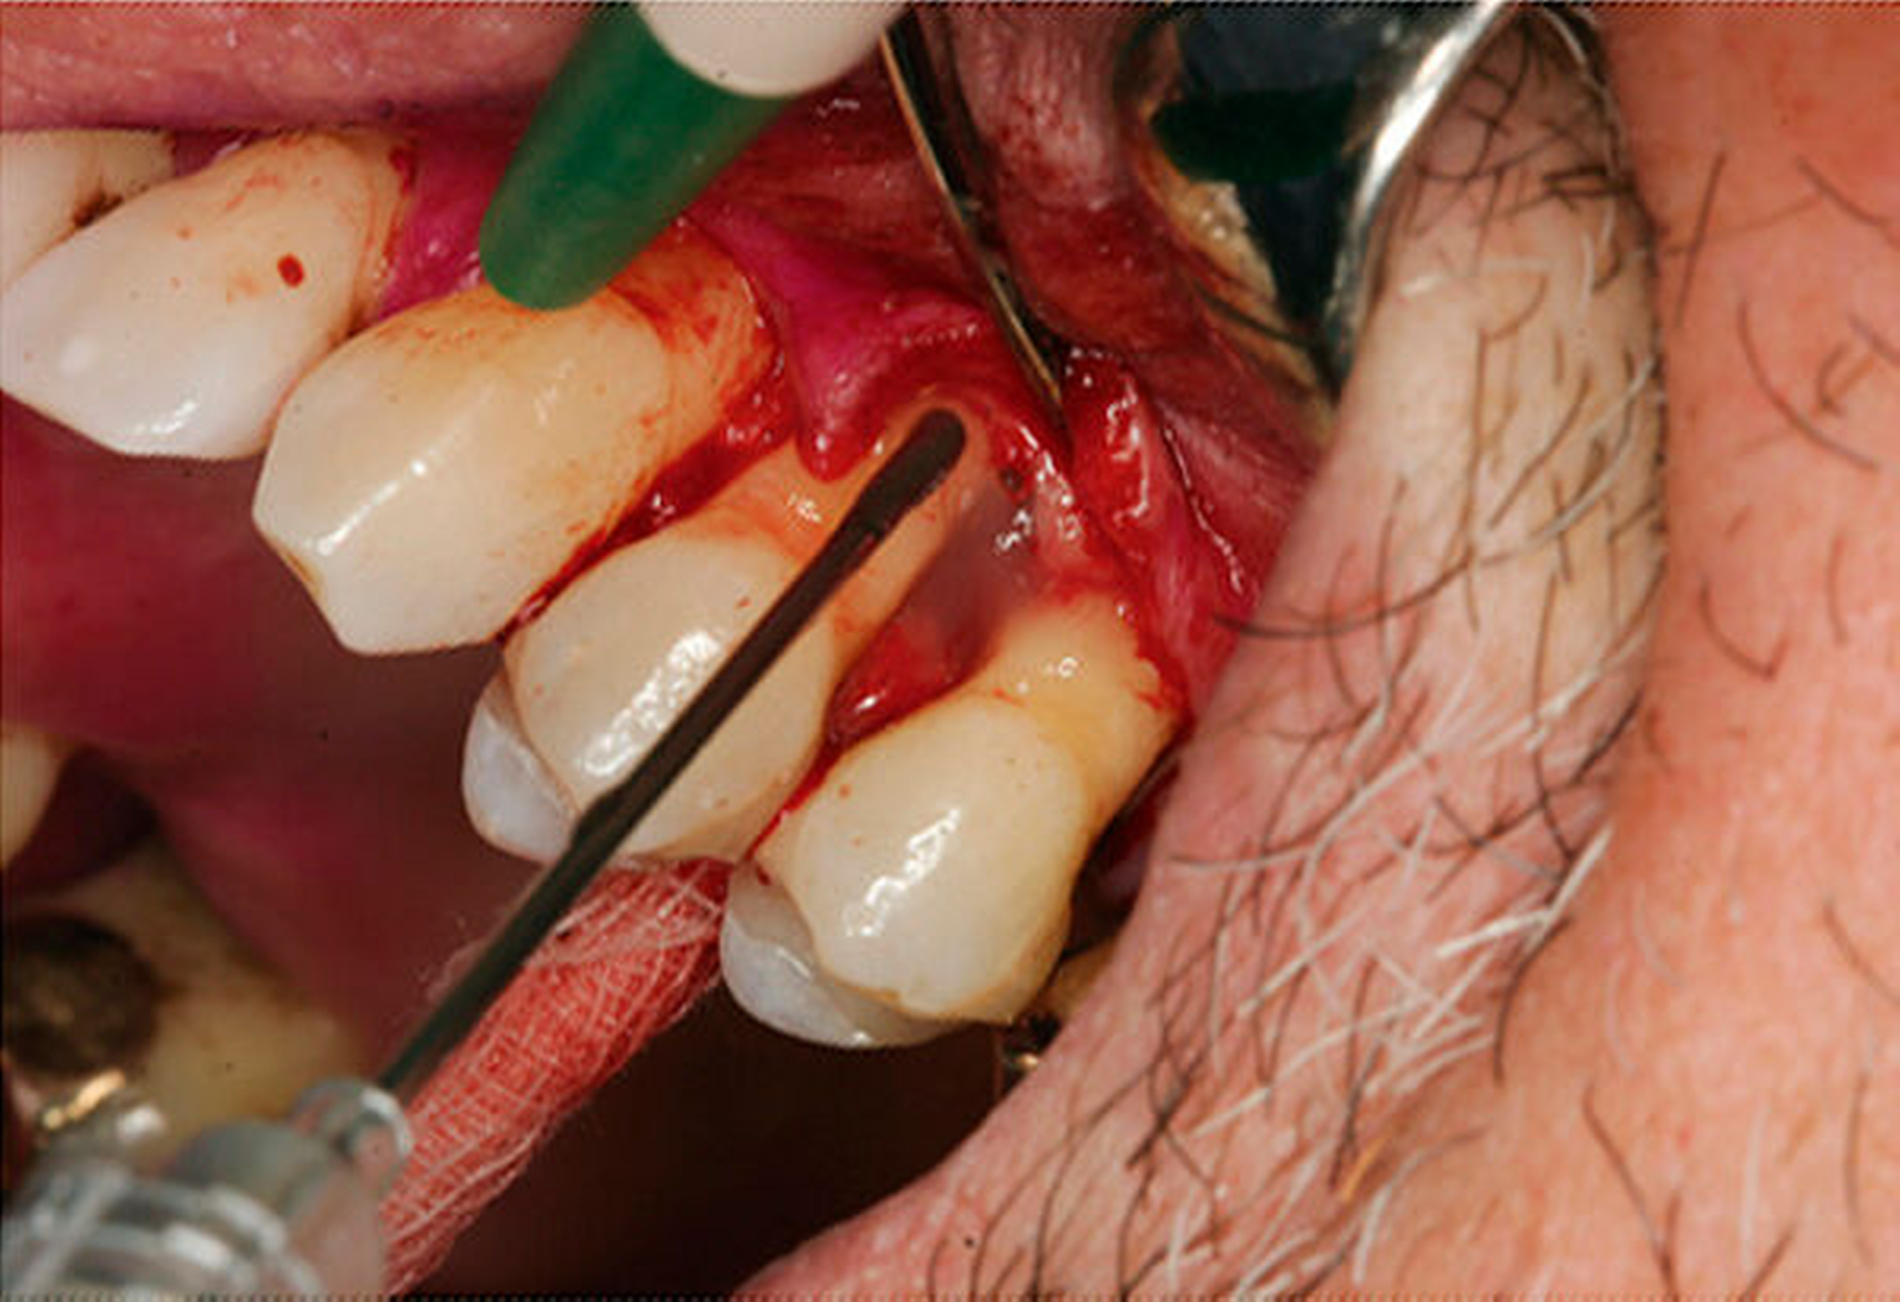

Werden verschiedene Zugangslappentechniken wie Instrumentierung unter Sicht mit Lappenbildung (Open Flap Debridement, OFD), Lappen mit paramarginaler Inzision (modified Widman Flap, MWF, Abbildungen 1 und 2), und Papillenerhaltungslappen (Abbildung 3) als konservative parodontalchirurgische Interventionen ohne signifikanten Weich- und Hartgewebsverlust hinsichtlich der Reduktion der TST verglichen, so bestehen kaum Unterschiede. MWF und OFD wurden in drei randomisierten klinischen Studien verglichen und nur eine davon hatte eine höhere Taschensondierungstiefenreduktion durch den MWF zum Ergebnis [Sanz-Sanchez et al., 2020].

Diese Fragestellung in der Leitlinie widmet sich dem Vergleich der Ergebnisse nach Lappenoperation mittels Zugangslappen (Abbildung 3), also Lappenbildung ohne gezielten Gewebsverlust, und resektiver Parodontalchirurgie – mit gezieltem Gewebsverlust, jedoch ohne zusätzliche Materialien zur parodontalen Regeneration [Polak et al., 2020]. Dabei werden alle chirurgischen Verfahren mit Resttaschen ab 5 mm nach vorheriger subgingivaler Instrumentierung verglichen. Bei der Betrachtung werden MWF (Abbildung 1), Excisional New Attachment Procedure (ENAP) in der Gruppe der Zugangslappen geführt. Die Gruppe der resektiven Parodontalchirurgie besteht aus auch zum Teil älteren Verfahren mit deutlicher Veränderung der Gingiva- und der Knochenkontur.